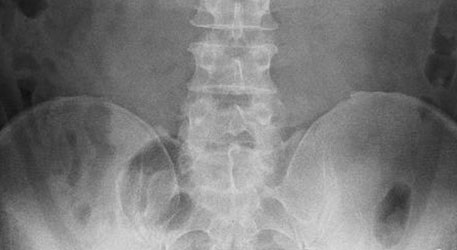

レントゲンでは分からない疾患がある

これらはレントゲンやMRIなどの画像診断では診断ができない疾患です。

さらに厄介なことに、例えばMRIで「椎間板ヘルニア」が見つかったとしても、

■無症状にも関わらず、腰椎椎間板ヘルニアは76%の人に存在する

ことが分かっています。

つまり、坐骨神経痛の本当の原因が、梨状筋症候群やハムストリング症候群などの「画像診断で分からない」疾患だったとして、たまたま腰にヘルニアが見つかってしまえば

「あなたの坐骨神経痛はヘルニアによるものですね」

と誤った診断を受けてしまうことになるのです。